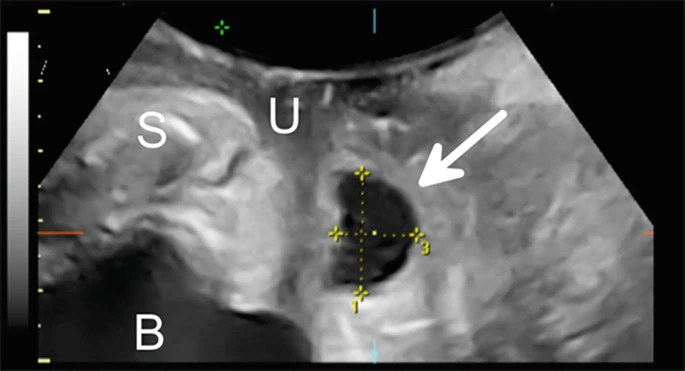

图 4.18

经阴唇 3D 超声在正中矢状面(箭头)成像的尿道憩室。S, 耻骨联合; B、膀胱;你,尿道。由悉尼大学 Hans Peter Dietz 教授提供